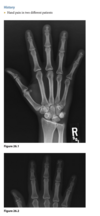

A 21-year-old man with worsening pain in the left wrist after an injury 6 months earlier (Fig. 2.13.1).

Figures 2.13.2 and 2.13.3 are of a 46-year-old man with wrist pain

Anteroposterior view of the left wrist

(Fig. 2.13.1) shows an ulna that is shorter than the

radius (i.e., negative ulnar variance or ulnar minus

variance) and a lunate that is sclerotic and some-

what irregular in shape.

Kienböck disease (i.e., lunatomalacia)

Kienböck disease, or lunatomalacia, is

osteonecrosis of the lunate. It is most common in

­ patients 20 to 40 years old and has a predilection

for the dominant hand in individuals involved

in manual labor.

Cause unknown

shortened ulna

in relation to the radius (i.e., negative ulnar variance

or ulnar minus variance) is seen in up to 75% of pa-

tients with lunatomalacia and is considered a major

cause of the disorder

The imaging findings, which do not always corre-

late with the patient’s symptoms, include increased

density or sclerosis of the lunate and, eventually, alteration in the normal bony shape with collapse

on radiographs.

For example, in a 46-year-old

man with wrist pain, a coronal T1-weighted image

(Fig. 2.13.2) demonstrates low signal intensity in

the lunate (arrow) and negative ulnar variance. The

gradient-recalled echo MR image (Fig. 2.13.3) shows

the signal intensity within the lunate to remain low

(arrow). These features are diagnostic of osteone-

crosis (i.e., Kienböck disease). Surgical intervention

includes lunate replacement, radial shortening, and

ulnar lengthening.